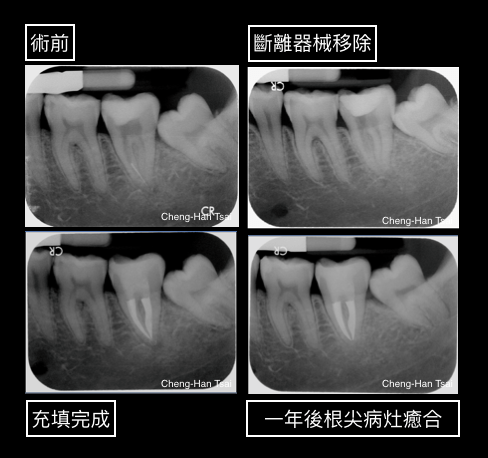

讓我們來看以下一個病例,病患因後牙根管治療中還是有不適及根尖感染的狀況,因而轉診來接受評估:

斷離器械是每個牙醫師在進行根管治療的過程中可能產生的風險,但是否需要移除斷離器械還需由專科醫師配合臨床症狀診斷評估;大部分若要進行移除斷離器械,需要根管治療專科醫師使用電腦斷層、顯微鏡、及超音波器械的輔助檢查及治療。